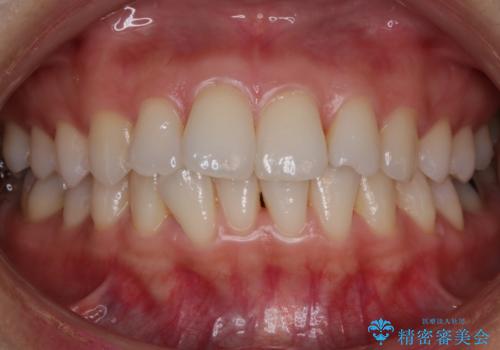

[マウスピース矯正] がたがたの歯並びをきれいにしたい

![[マウスピース矯正] がたがたの歯並びをきれいにしたいの症例 治療前](https://seimitsushinbi.jp/wp/wp-content/uploads/2025/06/0d238550c8a0fddc4de7b2c337c6c786-500x350.jpg?v=1750323380)

![[マウスピース矯正] がたがたの歯並びをきれいにしたいの症例 治療後](https://seimitsushinbi.jp/wp/wp-content/uploads/2025/06/IMG_0002-2-500x350.jpg?v=1750323305)